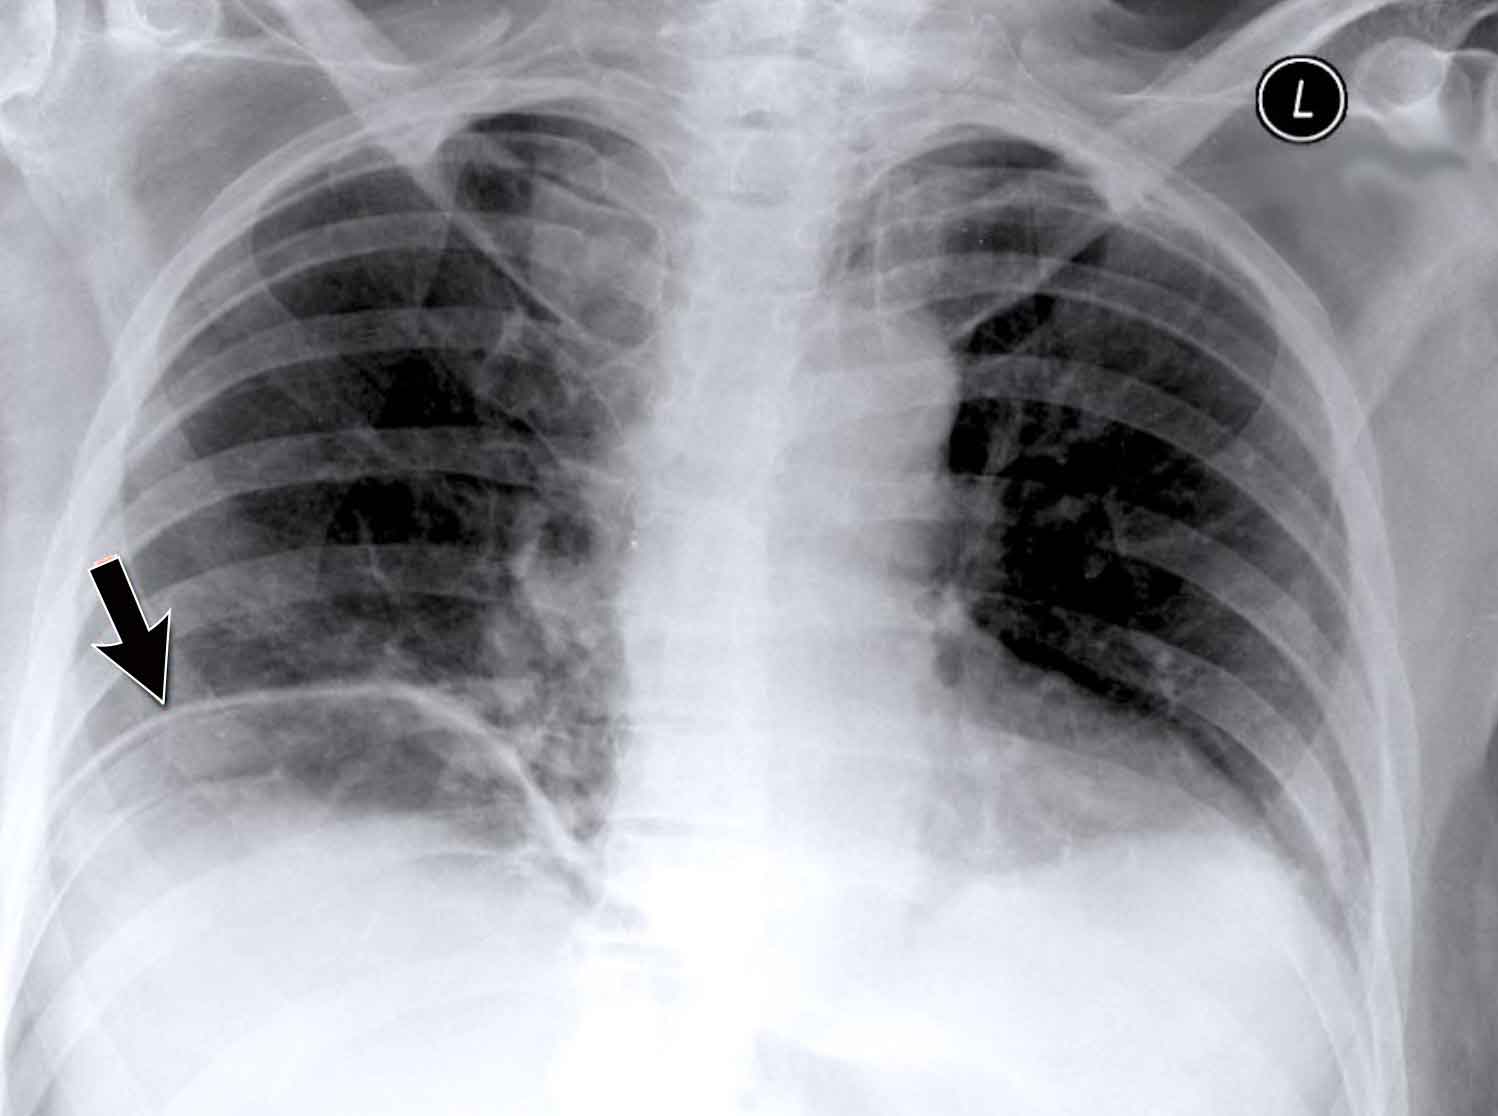

Case Example: Subtle Signs of Congestive Heart Failure

Begin by reviewing these current chest radiographs.

Based solely on these images, one might suspect congestive heart failure (CHF), though the findings are subtle.

Now review the previous study…

Scrolling between the current and prior films significantly increases diagnostic confidence in your diagnosis of congestive heart failure.

Key comparative findings include:

• Cardiac size: Slightly increased compared to the previous study; however, cardiomegaly was already present.

• Pulmonary vasculature: Mild vascular engorgement suggesting elevated pulmonary venous pressure.

• Interstitial markings: Subtle signs of interstitial edema .

• Pleural effusions: Bilateral small effusions, with subtle changes in the inferoposterior borders of the lower lobes, suggesting fluid accumulation.